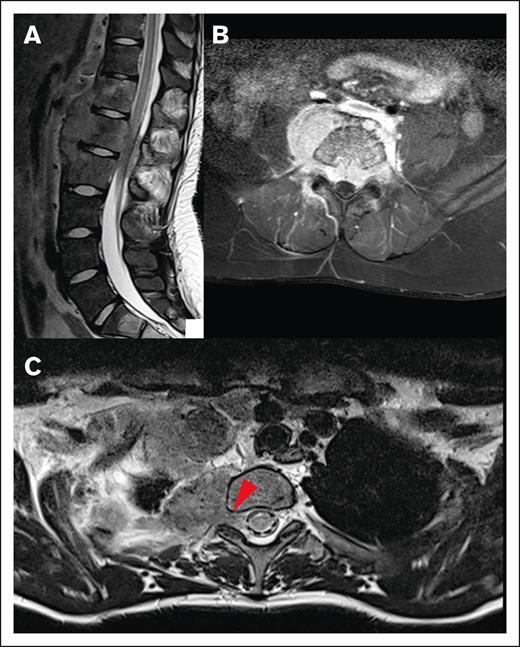

Most CNS lesions demonstrated an adequate metabolic response at IRA, with 89.1% PET negative (Deauville score 1-3) and 10.9% remaining PET positive (Deauville score 4 or 5; Figure 6). Only 1 of the CNS lesions that remained PET positive at IRA was irradiated, and none of these lesions were sites of relapse. Two CNS lesions (3.6%) that were PET negative at IRA (Deauville 1 and 3) were associated with relapse, and neither received irradiation. Thirteen CNS lesions (23.6%) in 13 patients received irradiation, and none were sites of disease relapse. These results have been summarized in Figure 7.

Staging and response assessment. Imaging at staging shows a large paraspinal mass (A, MRI) with intense glucose metabolism (B, 18F-FDG-PET/CT; red arrows = lymphoma; white arrows = normal kidneys). The mass originates from the bone and extends into the neuroforamen and the spinal canal (A-B). After 2 courses of OEPA chemotherapy, 18F-FDG-PET shows a good metabolic response (C, maximum intensity projection; red circle surrounds the slight residual uptake of the former CNS lesion; [D-E] 18F-FDG-PET/CT; same height as panel B; minimal glucose metabolism within the residual mass [red arrows]).